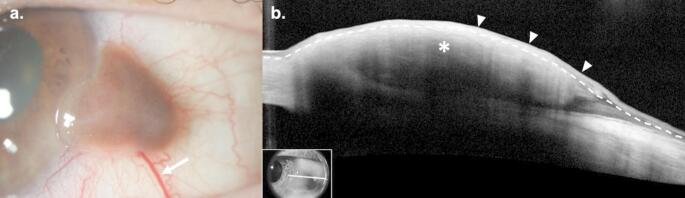

Purpose of review: Subepithelial lesions of the ocular surface represent a diverse group of pathologies which may be difficult to diagnose clinically. Some of these lesions are relatively uncommon, may result in systemic manifestations, or occur secondary to systemic disease. The purpose of this review is to summarize current approaches to the diagnosis and management of six subepithelial conjunctival lesions.

Recent findings: The standard for the diagnosis of subconjunctival lesions remains histopathologic evaluation; however, high-resolution anterior segment optical coherence tomography (HR-OCT) is a useful supplemental diagnostic tool that may facilitate diagnosis. Recent advancements in the management of subconjunctival lesions include targeted systemic therapies in conjunctival melanoma and ultra-low dose radiation radiotherapy in conjunctival lymphoma.

Summary: The development of HR-OCT has provided clinicians with valuable supplemental diagnostic information to guide the diagnosis of subepithelial lesions. Additionally, novel treatment modalities may provide an alternative to traditional surgical interventions in some pathologies.